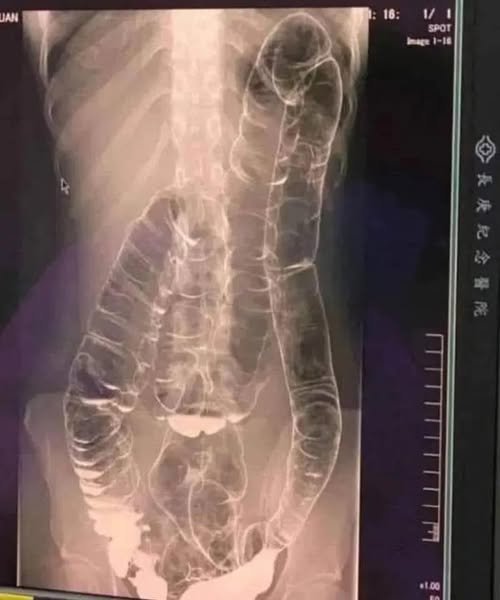

A saturated colon

When you don’t have regular bowel movements, waste builds up in the colon. The result: extra pressure that can cause pain, bloating , and, in severe cases, terrible complications.

- Colon distension: Over time, the colon weakens its elasticity and becomes increasingly difficult to remove stools.

- Bowel obstruction: In extreme cases, fecal matter can completely block the intestine, demanding emergency surgery .